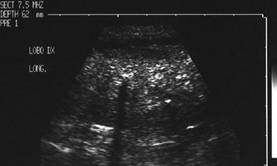

Lob drept , proiectie longitudinala si trasversala .

Barbat de 44 ani. Nodul mare in lobul drept si istm de 31x44x44mm, (30 cc) cu contur net, hipoecogen, neomogen, cu macrocalcificare.

Examn citologic: neoplazie oncocitara (a c. Hurthle).

Examen histologic postoperator: adenom cu celule Hurthle.